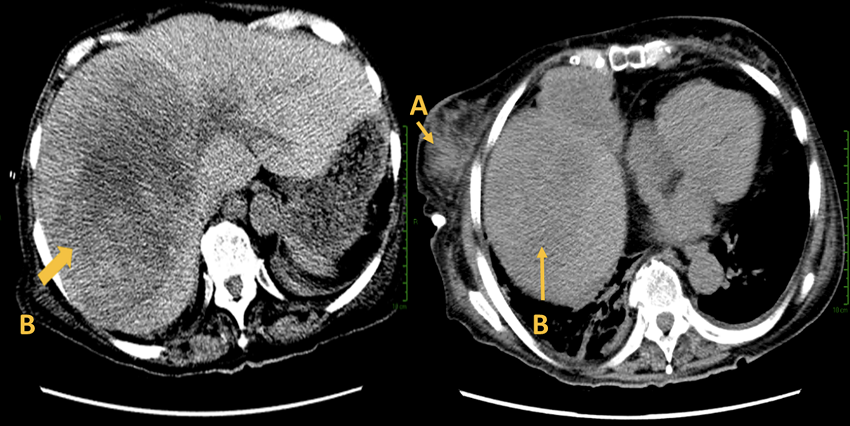

Se realizó tomografía computarizada como estudio de extensión, con cortes axiales, en fase simple, el cual reportó estructuras de la base del cuello sin alteraciones, calcificación en válvula aórtica, con morfología y tamaño normales, glándulas mamarias asimétricas, sin evidencia de adenomegalias mediastinales, cambios degenerativos en estructuras óseas. Se reportó una lesión hepática (Figura 3), la cual se protocolizó, se realizó biopsia y al resultado histopatológico se encontró un segundo tumor primario, el cual resultó un melanoma hepático. Se descartó la presencia de linfomas en otras localizaciones.

A pesar de la respuesta adecuada y el control del LNH, un año y medio después presenta progresión del segundo tumor primario, el cual comprometió el pronóstico. Se realizó una tomografía axial computarizada, en donde se apreció derrame pleural del 60 % (Figura 3), por lo que se realizó pleurodesis, la cual drenó 600 cc de líquido serohemático, por lo que se colocó un catéter tunelizado.